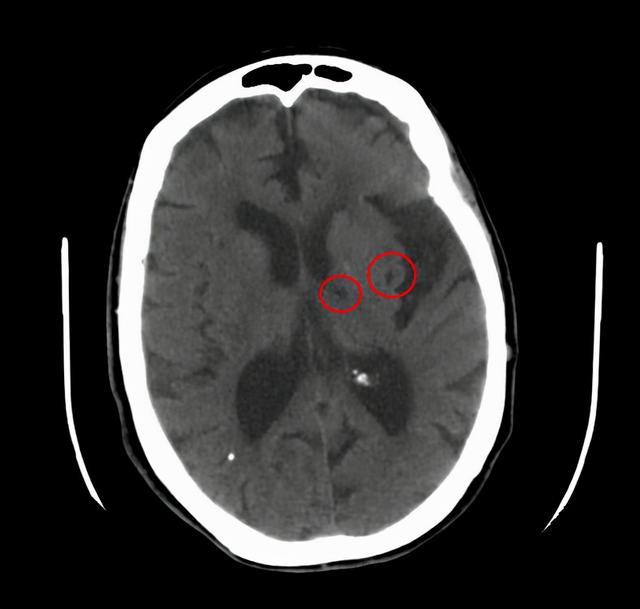

二、无症状的腔梗。

如果出现腔隙性脑梗死该怎么办呢?

当然,这个问题其实也应该分情况讨论。

如果有了具体症状,腔梗还是该治疗的,比如一侧肢体的运动感觉障碍,这个时候要小心,具体怎么治疗还是听医生的吩咐比较好。

但是如果没什么表现,仅仅是在体检或者在检查其他疾病的过程中发现有腔梗,这个时候该怎么办呢?

临床当中这种情况是很常见的,我们称为无症状的腔隙性脑梗死,对于这类患者,请您别害怕。

虽然我们称之为脑梗死,但他对我们的危害并不大,只需要改善生活方式,积极预防下一次腔梗就可以了。

需要用药吗?需要用治疗脑梗死的扩血管药物吗?是不是应该活血化瘀呢?

都不用,千万别被骗。